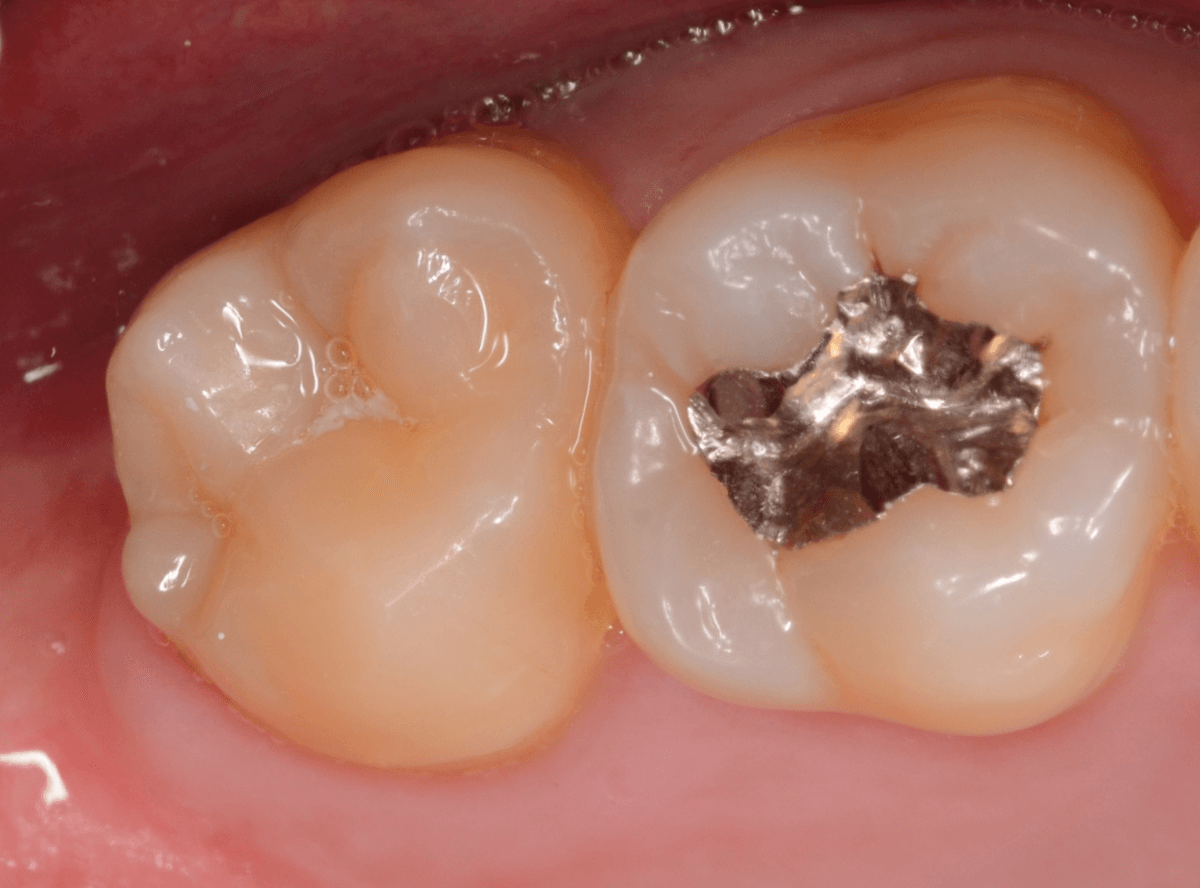

Case.4 2年間メンテナンスを中断している間に、深く虫歯が進行!

定期メンテナンスを2年間中断後に、来院された患者さんです。

見た目は手前の歯との間の小さな虫歯に見えますが、

「普段は痛くない」

「食事の時に物がつまる」

「物がつまった時に噛むと痛い」

・・・と、自覚症状は乏しいが、実際は大きな虫歯の場合の症状あるあるの訴えでした。

レントゲン写真で虫歯の状況を確認します。

赤い線が虫歯の部分、青い線が歯の神経の部分です。

思った通り、入り口の小さなすき間の中は、神経まで達してしまいそうな大きな虫歯になっていました。

歯を削り始めると、すぐに大きな穴が出てきました。

ある程度虫歯を除去したところで、う蝕検知液で染め出してチェックします。

まだまだ虫歯が残っていますね。

取り残しがないように、しっかり除去する必要があります。

虫歯を全て除去したところです。

神経が少し見えるところまで虫歯が進行していました。

神経を保護するお薬をつめた後、蓋をしてしばらく痛みが出ないか、経過観察します。

痛みが出て止まらないようでしたら、神経を除去する治療が必要になります。

定期メンテナンスを中断しなければ、このような状況にはならなかった事が本当に悔やまれます。

しばらく経過観察後、幸運にも特に症状なく経過しましたので、型どりをして、つめもの(メタル・インレー)で修復する事ができました。

この後、サボらず定期メンテナンスに来院いただくよう、念を押して治療終了となりました。